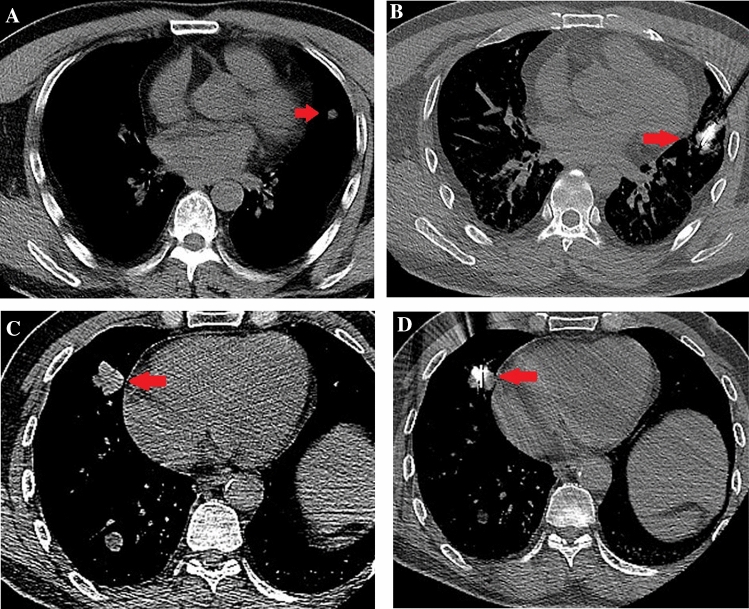

Based on the results of previous experimental and clinical studies, NSCLC adjacent to the pericardium was defined as index tumors within a distance of 1.0 cm from the pericardium, according to CT scans [18]. Axial images were evaluated using a picture archiving and communication system under magnification. The tumors were classified into two groups, according to their distance from the heart: group A comprised tumors at a distance of 1–10 mm (i.e., tumors that were close but not contiguous with the pericardium), and group B included tumors at a distance of 0 mm (i.e., tumors that were contiguous with the pericardium) (Fig. 2).

A Chest computed tomography (CT) obtained prior to microwave ablation (MWA) shows a 1.2-cm well-defined round tumor (red arrow) in the left lobe (lesions that were not contiguous to the pericardium). B In the supine position, MWA was performed on the lung tumor adjacent to the pericardium (red arrow). C CT obtained prior to MWA shows a 2.8-cm well-defined round tumor (red arrow) in the right lobe (lesions that were contiguous to the pericardium). D In the supine position, MWA was performed on the lung tumor adjacent to the pericardium (red arrow)